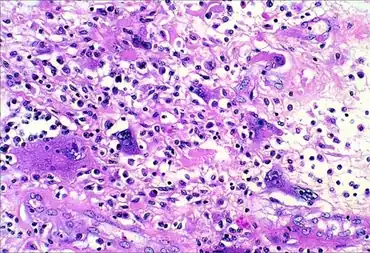

Micrograph of undifferentiated pleomorphic sarcoma (H&E stain)

Microscopic exam of undifferentiated pleomorphic sarcoma shows nuclear pleomorphism

UPS is a diagnosis of exclusion (a diagnosis reached by the process of elimination) because the histopathology of this disorder's tumors is non-specific. UPS tumor cells are undifferentiated (i.e. do not resemble any particular cell type) and pleomorphic (i.e. highly variable in size, shape, and/or color) when examined microscopically. Therefore, the diagnosis of UPS is commonly based on detecting a specific set of proteins that are expressed by UPS tumor cells but not by the cells of other undifferentiated and pleomorphic tumors or visa versa (see Diagnosis section).[11]